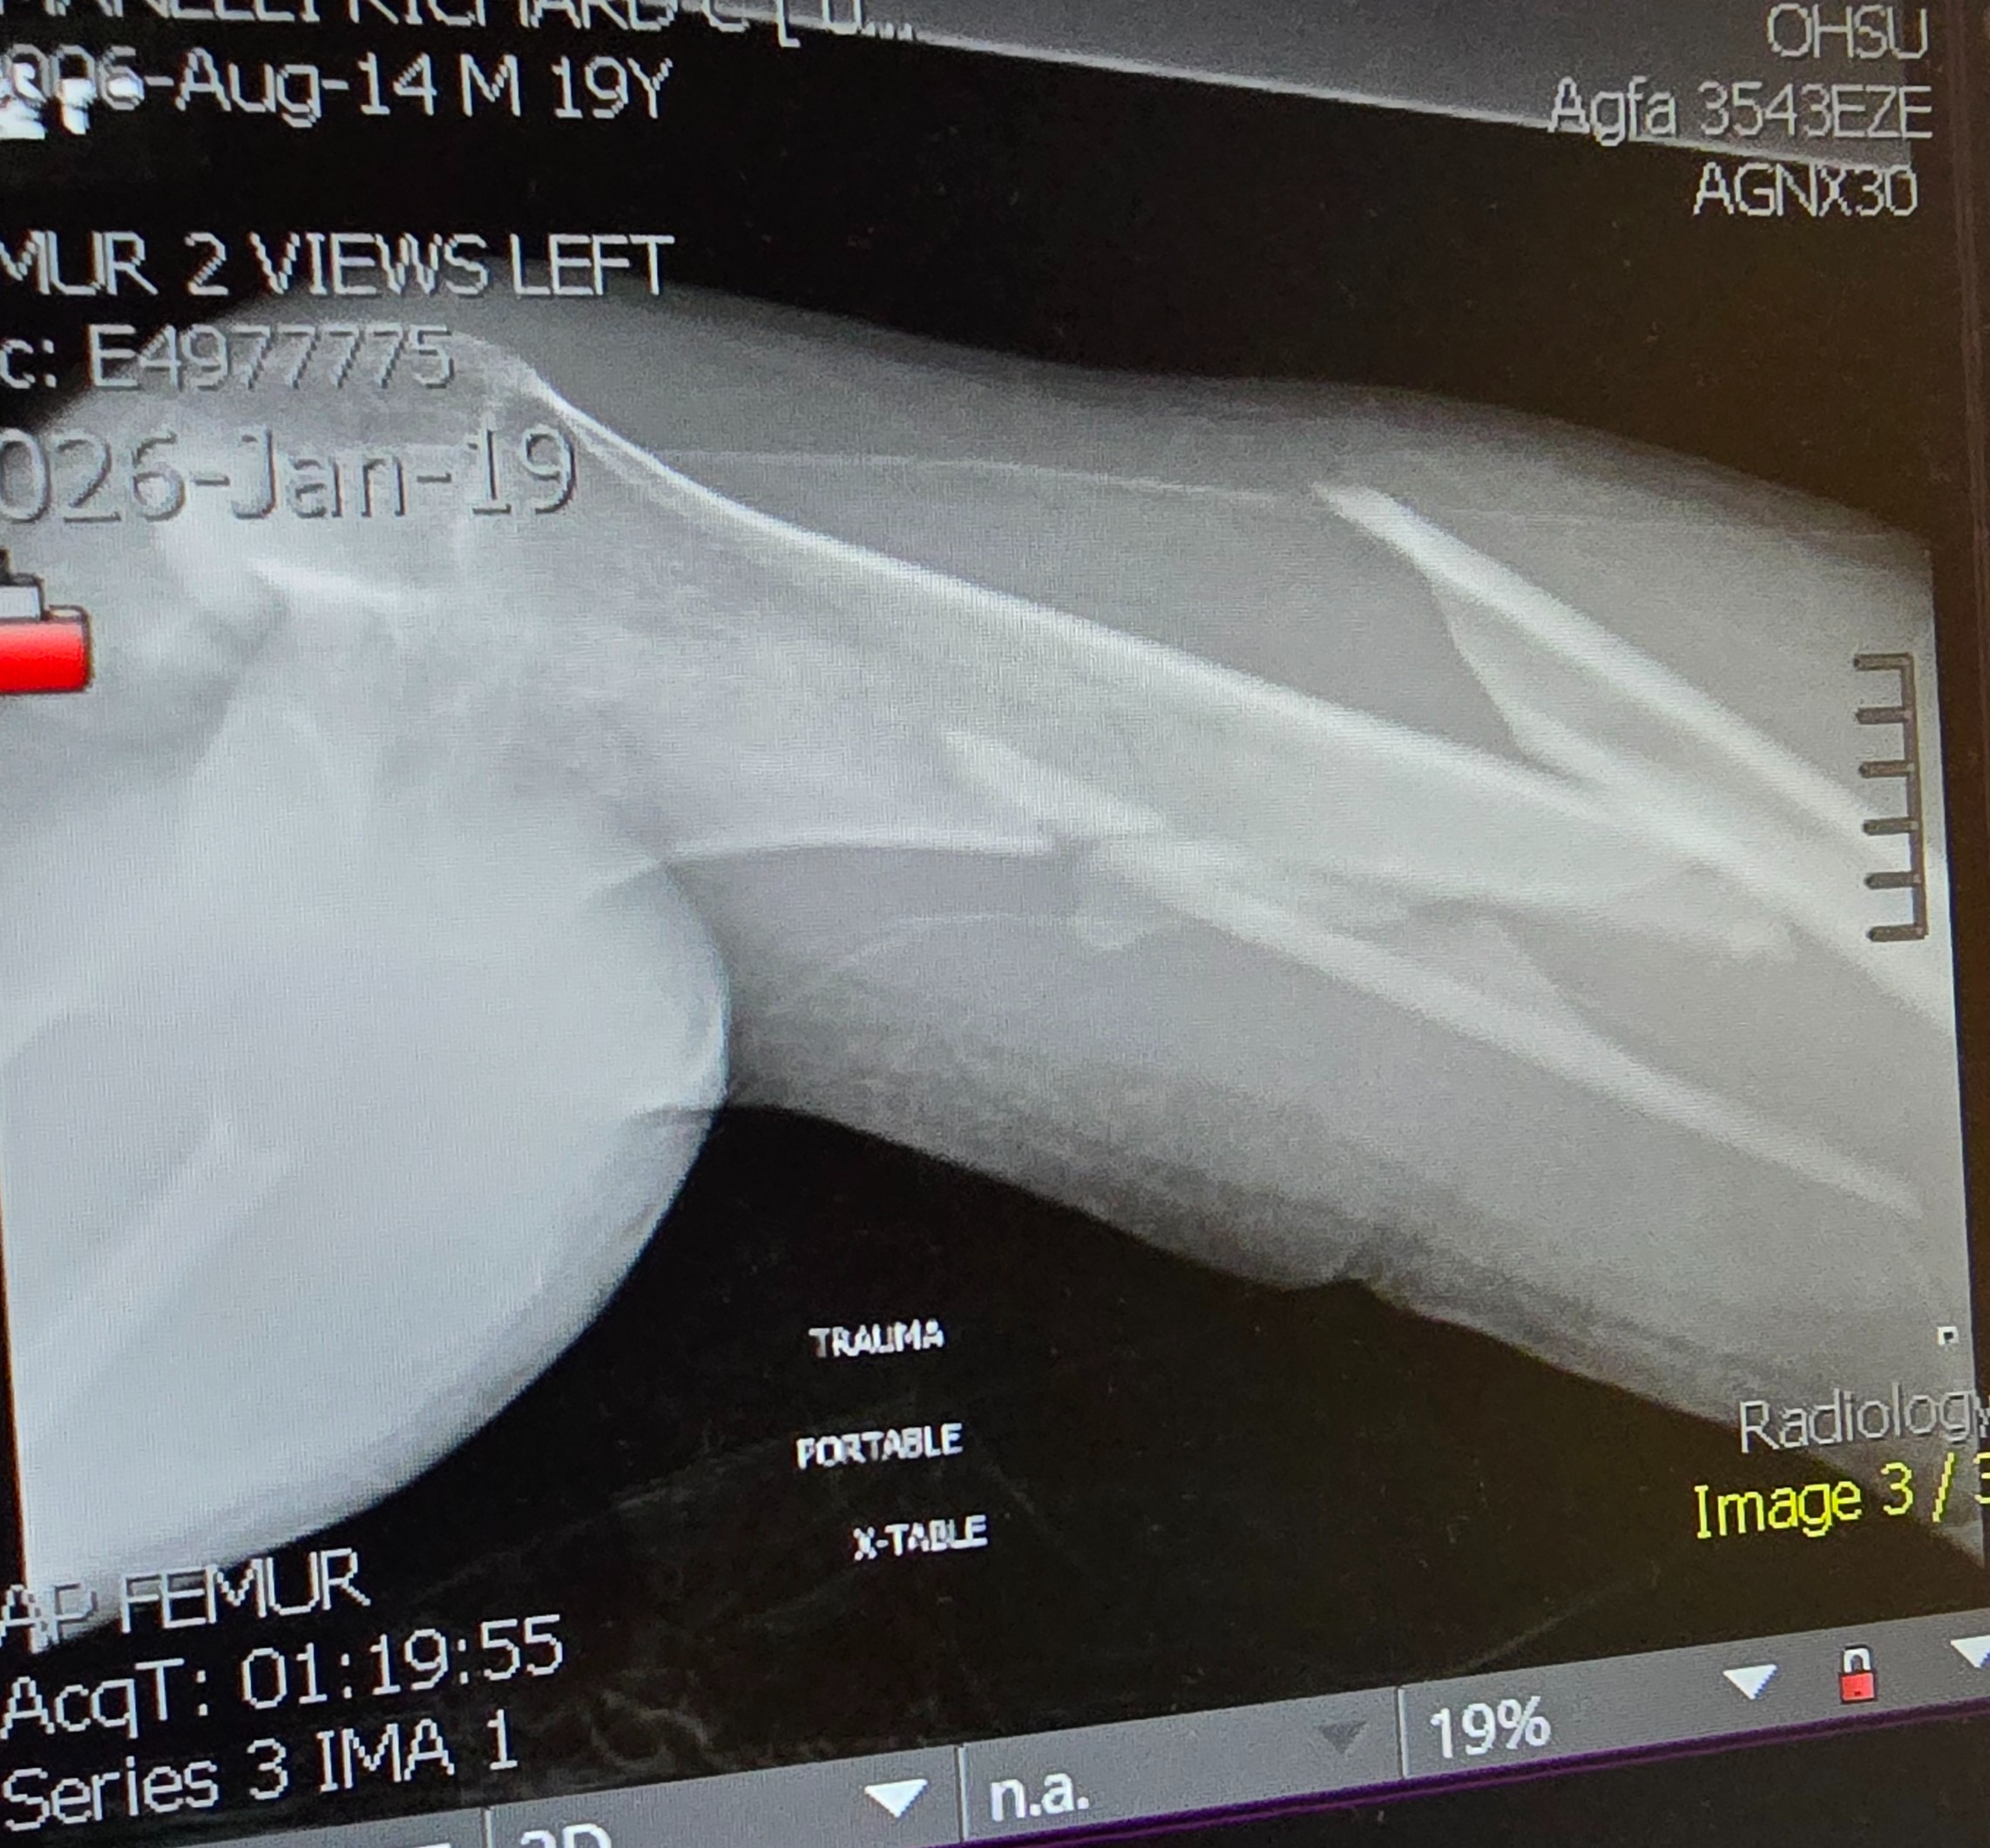

Even though he was wearing his seatbelt, the entire impact hit his left side. His left arm was shattered into multiple pieces, causing severe nerve damage. His left femur was broken into three pieces. He also struck his head against the window.

He was rushed to the hospital, where he spent a long night in unbearable pain before undergoing nearly eight hours of emergency surgery the next morning. Surgeons worked tirelessly to reconstruct his arm and leg. Today, Cole lives with metal rods and screws permanently placed in both his arm and leg.